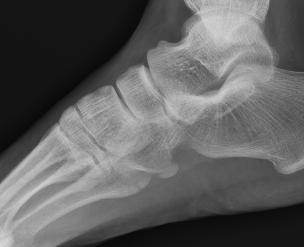

Xray

Displaced os peroneum suggests complete P longus tear